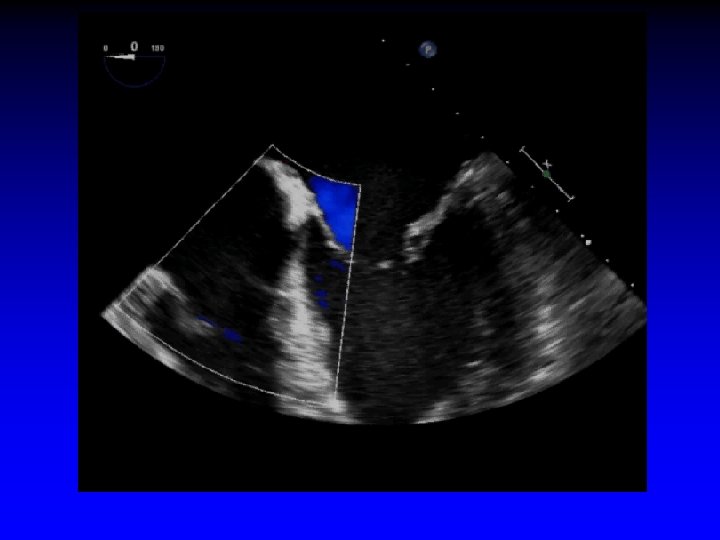

Case 1 Ruptured cords P 2

1. 6 cm +. . . + Gastric short-axis view (PSR view)